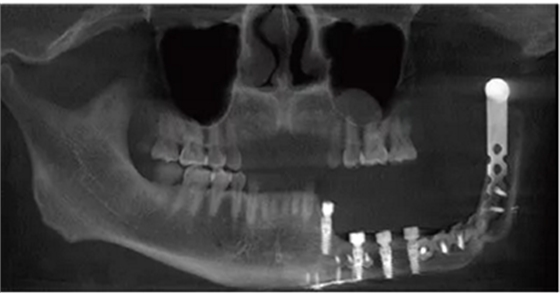

種植體植入后拍攝錐形束CT(cone-beam computed tomography,CBCT)顯示種植體在位,復(fù)合基臺(tái)對(duì)接在位,骨愈合良好(圖6)。

卸下患者口內(nèi)的35~37臨時(shí)個(gè)性化復(fù)合基臺(tái)保護(hù)帽和34復(fù)合基臺(tái)保護(hù)帽,注射生理鹽水沖洗種植體及周圍軟組織,口內(nèi)試戴純鈦鑄造桿(圖15A),拍攝CBCT示鑄造桿與種植體復(fù)合基臺(tái)對(duì)接良好(圖15B)。將34~37膠托活動(dòng)義齒就位于鑄造桿上部Locator附著體,囑患者做正中咬合及側(cè)方咬合,調(diào)磨咬合高點(diǎn),拋光,完成最終修復(fù)體的戴入(圖15C、D)。囑修復(fù)后修復(fù)體及牙周維護(hù)。